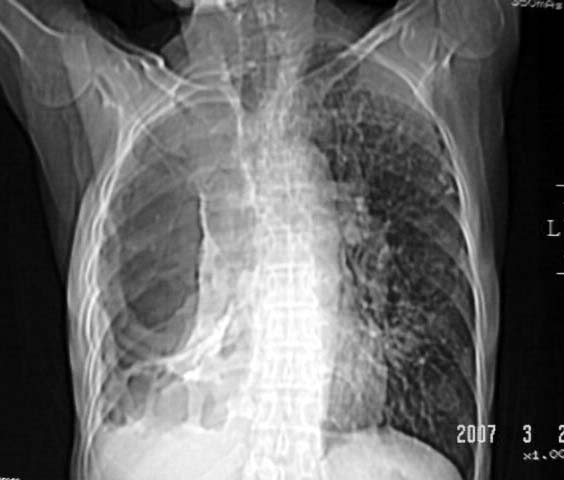

以下是引用dyqct在2007-3-2 22:04:00的发言:[br]考虑:1、右侧毁损肺伴支气管胸膜瘘(多条支气管与胸腔相通、液气胸);[br] 2、左肺浸润型肺结核。[br][br][br][br]